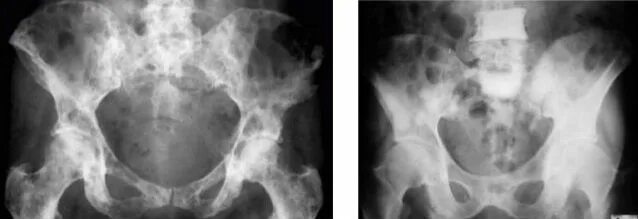

Метастазы в тазобедренном